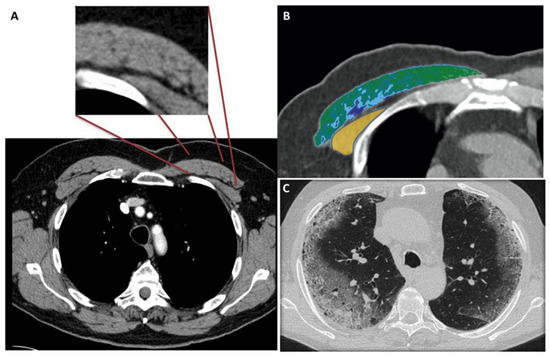

Figure 1 shows the modality of PMD and PMA evaluation. Figure 2 and Figure 3 show the examples of two patients enrolled in the study.

Figure 1A shows the CT-slice selection and the pectoral analysis. Figure 1B shows the pectoral muscle area (34.2 cm2) and pectoral muscle density (30.2 HU) analysis of the pectoralis major (green-blue area) and minor (yellow area). Figure 1C shows the corresponding lung disease (pneumonia severity index score: 7). The patient had a short ICU stay, and he had successful extubation.

Figure 1. (AC) 56-year-old male with COVID-19.

Tomography 08 00034 g001